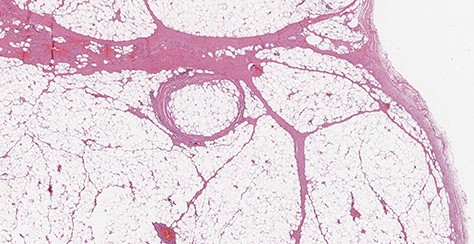

Microscopic transverse section revealing a benign tumor composed of a large amount of mature adipocytes with a flat peripheral nucleus without atypia, surrounded by fibrous tissue and containing rare blood vessels (H&E stain, ×10).